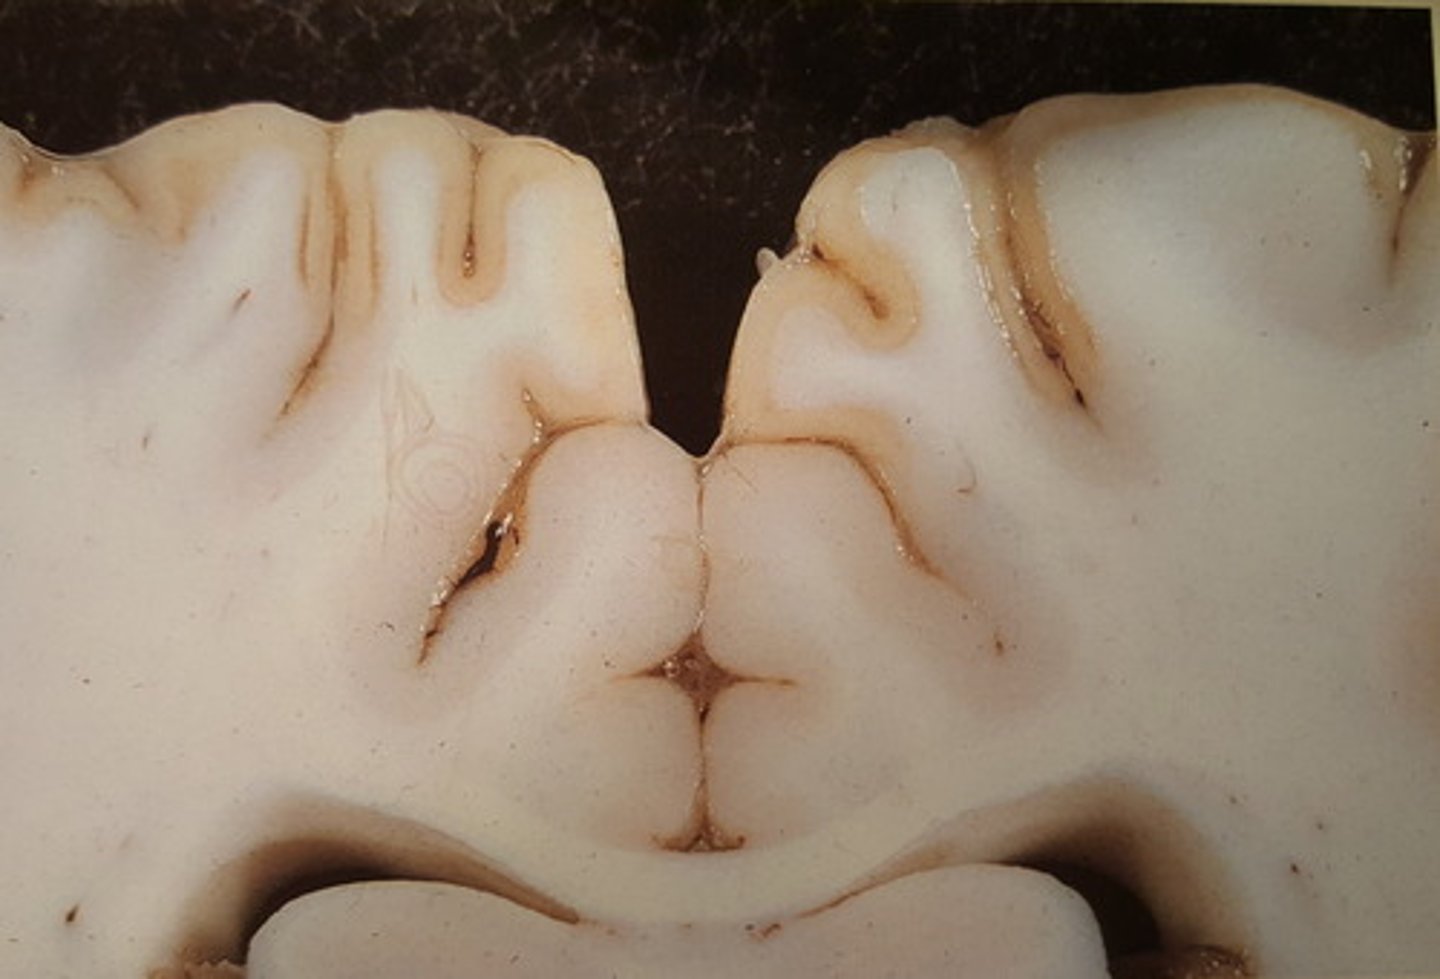

polioencefalomalaci (cerebrokortikal nekrose) med begyndende sekvestration

Brunish misfarvning på cerebral cortex

Hjerne fra okse. Patoanatomisk diagnose?

polioencefalomalaci (cerebrokortikal nekrose)

Pga. B1- vitamin (thiamin) mangel.

Hjerne fra okse. Patoanatomisk diagnose og mulig ætiologi?